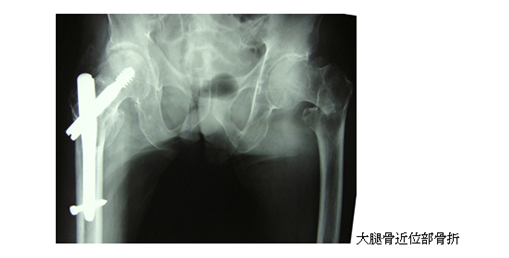

非定型大腿骨骨折

それ以外にも骨粗鬆症性の難治性骨折や、脊椎椎体骨折などに対する薬物療法や手術治療の効果についての臨床研究を行っております。また、近年報告されるようになった非定型大腿骨骨折や骨壊死と骨粗鬆症の関連に関しても、その原因を解明するために臨床研究を行っています。